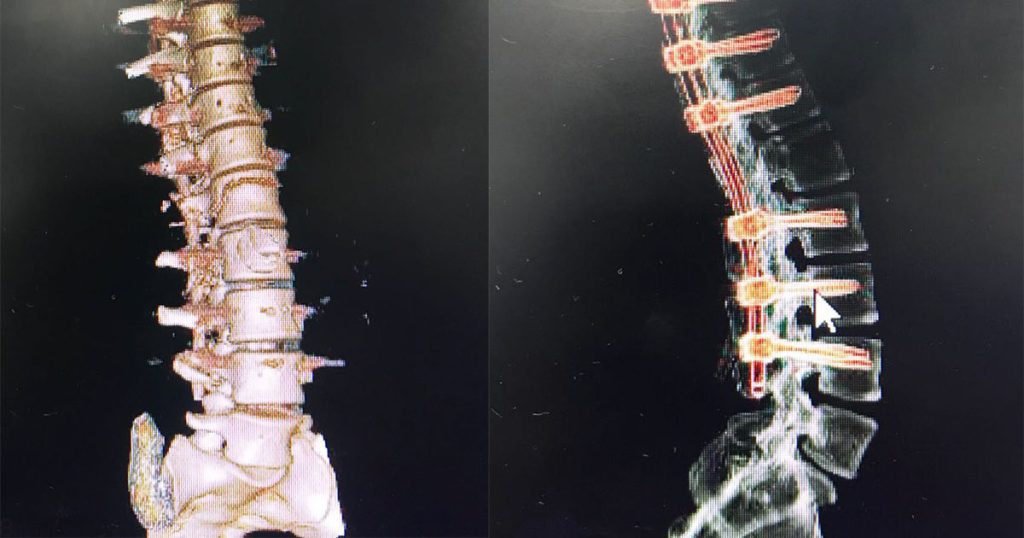

La especialidad de neurocirugía de Medical lideró en la institución un proceso de traumatología con una complejidad severa en una paciente adulta. La patología presentada fue un trauma raquimedular el cual evidenció desplazamiento de vértebras y médula espinal de su eje central.

Una vez diagnosticada la patología por los especialistas de la clínica, se procedió inmediatamente a realizar un plan el cual consistía en rehabilitar la columna de la paciente debido a que se presentaba una pérdida de movilidad en sus miembros inferiores a causa de su traumatología.

Una vez establecido el caso, se realizó junta médica para determinar el plan y los pasos a seguir. Por ello, la especialidad de neurocirugía indicó una estabilización de unión toracolumbar con fijación transpendicular con fines ortopédicos y reducción de luxofractura por medio de una artrodesis.

Ante la gravedad del hecho se realizó la cirugía sin ningún tipo de complicación en el estado de salud de la paciente, teniendo como resultado una notoria mejoría al estabilizar vertebras y médula espinal dentro del eje central de la columna. Dicho caso se suma a los procedimientos de alta complejidad que se realizan en Clínica Medical. Una vez más se confirma que es una institución líder a nivel local y nacional en la atención de pacientes con trauma.